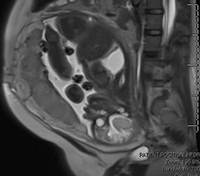

Fetal MRI

MRI is a noninvasive imaging test that provides detailed information about anatomic structures of the fetus. High-resolution images are taken rapidly using a “snapshot” technique. MRI pictures are obtained for evaluation using a magnetic field rather than radiation.

A fetal MRI can enhance the information obtained from a high-resolution fetal ultrasound and provide additional information about your baby’s diagnosis. It is performed in the second or third trimester of pregnancy. An MRI evaluation is used to evaluate abnormalities in your baby’s body, brain, and spine. It may also be used to confirm an ultrasound diagnosis or add significant diagnostic information in complex cases.

UR Medicine's Golisano Children’s Hospital is the only facility in Upstate New York with ultrafast fetal magnetic resonance imaging (MRI). UR Medicine's Pediatric Radiology is specifically trained in the care of pediatric patients.